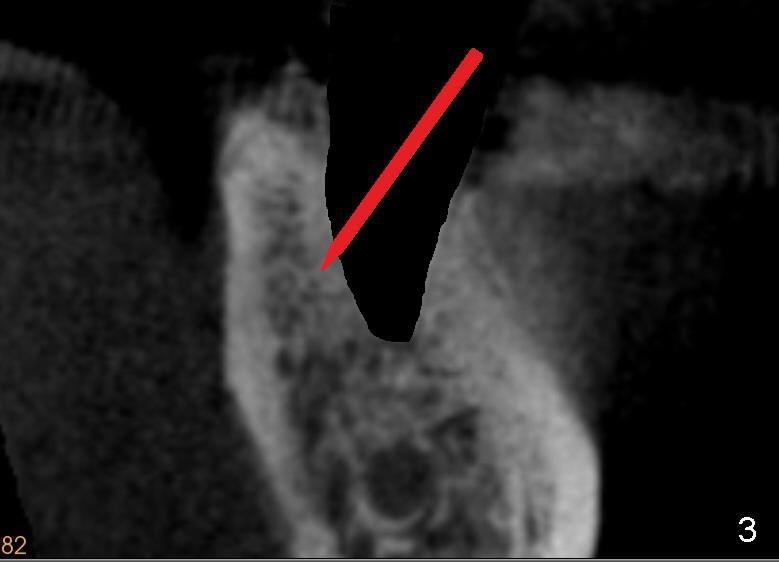

To overcome this problem, a pilot drill penetrates the buccal slope of the lingual wall (Fig.3 red line). Once the pilot drill gets "bite", change its direction to finish osteotomy (Fig.4). When subsequent drills are being used, lean each drill lingually, against "natural" tendency of the drill sliding buccally.